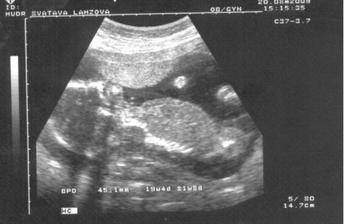

20. srpna - máme za sebou velký ultrazvuk a bylo to perfektní 🙂 Viděli jsme hlavičku, ručičky, nožičky, srdíčko, močový měchýř, páteř...Bobík byl celou dobu otočený čelem a krásně se nám ukazoval, dokonce i mával, ale to viděl jenom taťka a taky otvíral pusinku. Jen pohlaví zatím nevíme - seděl si na něm 🙂 Nevadí, počkáme, to je to nejmenší. Nádherné bylo slyšet z ůst paní doktorky - JE TO ZDRAVÉ MIMINKO.

31. srpna - kardioultrazvuk je za námi, srdíčko je uplně zdravé, bylo detailně prohlédnuto a vše je OK! 🙂 Ke konci prohlídky jsem se pana doktora nesměle zeptala, jestli by se nám nepodíval na pohlaví a světe div se - miláček se nám ukázal (sice jen na chvilku, ale přece) a budeme mít CHLAPEČKA

!!! Budeme mít ♥ Samíka♥. Těm, co tipovali holčičku jsi pěkně vytřel zrak Same! 🙂))

3. září - 4D Utz za námi (Sam váží 484g), byl to neskutečný zážitek se na chvíli podívat za Samem do jeho světa, musím na to pořád koukat (dostali jsme i DVD záznam). Je to nádherný chlapeček (znovu potvrzen), trošku stydlín, ale máš být po kom, že Samíku? 😉 Má krásnou tvářičku, ručičky, prstíky, nožky, ouška.., nosánek bude spíše po mámě, jsem moc pyšná! Už se ho nemůžu dočkat...